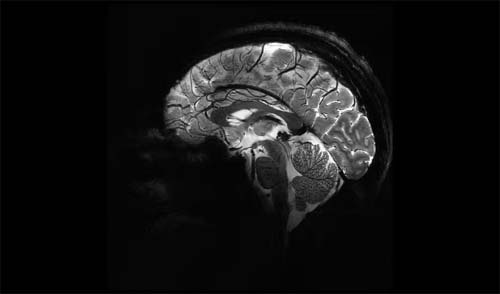

Novo estudo traça relação entre tamanho do cérebro, Parkinson e TDAH; entenda

Para a pesquisa, foram reunidas amostras de DNA e exames cerebrais de ressonância magnética que mediram o volume nas principais regiões do sub-córtex de quase 75 mil participantes de ascendência europeia.

Os pesquisadores descobriram associações entre o volume do cérebro e um risco maior de doença de Parkinson e de transtorno de déficit de atenção com hiperatividade (TDAH). As variantes encontradas explicam até 10% das diferenças no volume cerebral dos participantes, segundo o estudo.